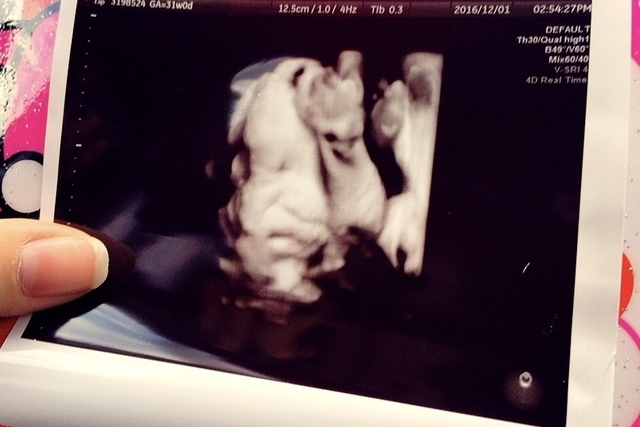

31週0日(31w0d・男の子)|まめんこ さん(32歳)

エコー写真撮影時のエピソード:

子宮に顔を押し付けて鼻ぺちゃです。3人目の妊娠ですが、何度見てもエコー写真はワクワクします。しかし、今回の子はなかなかいい顔を見せてくれなくて、どんな顔をしているのかとても楽しみです。妹が欲しいと言っていたお姉ちゃんも楽しみにしてくれています。